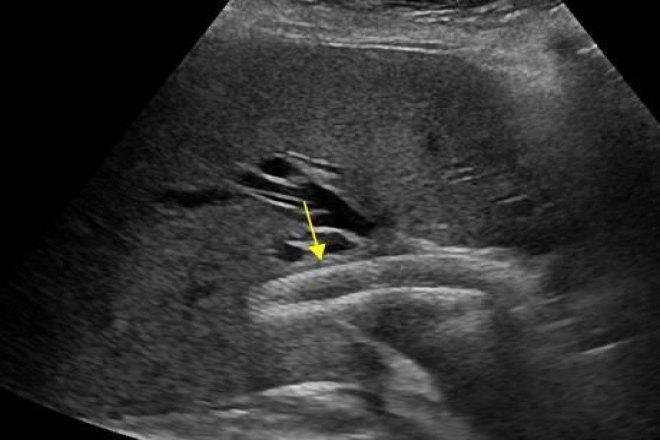

Carcinoma de vías biliares. Tumor de klatskin

Los cánceres biliares habitualmente cursan con obstrucción biliar. Aún así esta puede no ser completa y no producir el síntoma más frecuente, la ictericia, sobre todo en estadios tempranos. Por otra parte , en tumores proximales, una obstrucción segmentaria puede ocluir uno o varios segmentos aislados del árbol biliar intrahepático sin dar síntomas específicos. La comprensión de estas formas de presentación resulta de suma importancia ya que los estadios tempranos de esta enfermedad pueden no reconocerse.